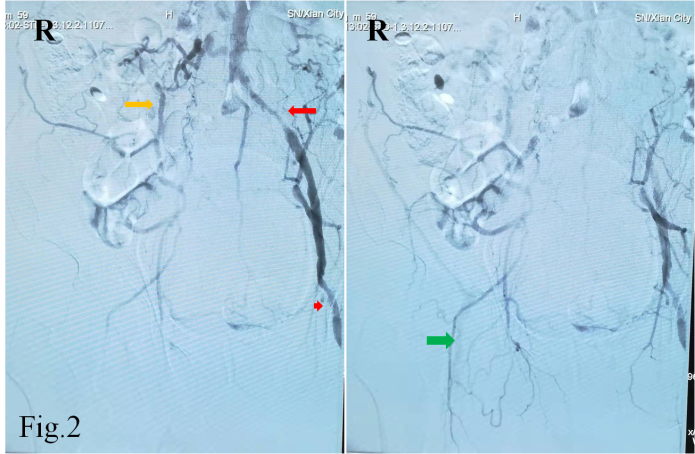

55岁的白先生因急性脑梗死入住21点游戏攻略站 神经内科,双侧颈部血管、锁骨上窝均可闻及血管杂音,为详细评估脑血管情况,拟行全脑血管造影检查。常规的脑血管造影检查首选右侧股动脉穿刺入路完成造影,但是该患者存在明确的右下肢间歇性跛行病史,双侧股动脉搏动触摸不到。下肢动脉超声提示双侧股动脉中度狭窄,股动脉、腘动脉等下肢血管动脉粥样硬化斑块形成。仔细评估后,考虑无法从股动脉穿刺进行造影检查。经神经介入医生周密准备,拟进行经右侧桡动脉穿刺完成脑血管造影及下肢血管造影检查。

经过导丝引导下,谨慎地将造影导管置于主动脉弓,造影显示Ⅱ型主动脉弓,介入医生顿感压力倍增。常规路径下(股动脉置管),Ⅱ型主动脉弓要比Ⅰ型主动脉弓操作难度复杂的多,颈部血管从主动脉弓发出角度、走形、迂曲度及造影导管在主动脉弓如何塑形、塑形成功率等等都会制约操作时间、顺畅性,稍有不慎可能导致主动脉弓斑块脱落、主动脉动脉夹层等情况发生。增加了在经桡动脉在Ⅱ型主动脉弓上超选造影的难度。经介入医生耐心、细致操作下,反复尝试降主动脉造影导管成型,逐步“逆行”完成全脑血管造影及下肢动脉造影。